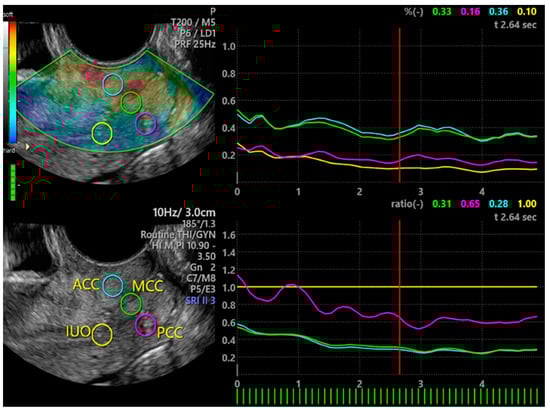

3.2. Elastography of the Cervix

| Cervical Compartments | Total (n = 79) | Pain (n = 58) | No Pain (n = 21) | p-Value |

|---|---|---|---|---|

| ACC Elasticity | 1.21 ± 0.27 | 1.22 ± 0.26 | 1.17 ± 0.30 | 0.779 |

| ACC % Deformation | 0.17 ± 0.09 | 0.18 ± 0.10 | 0.15 ± 0.08 | 0.285 |

| PCC Elasticity | 0.59 ± 0.38 * | 0.58 ± 0.38 * | 0.65 ± 0.38 † | 0.465 |

| PCC % Deformation | 0.11 ± 0.07 * | 0.10 ± 0.07 * | 0.11 ± 0.06 | 0.791 |

| IUO Elasticity | 0.77 ± 0.41 * | 0.72 ± 0.40 * | 0.92 ± 0.42 | 0.059 |

| IUO % Deformation | 0.10 ± 0.06 * | 0.09 ± 0.05 * | 0.13 ± 0.08 | 0.025 |

| MCC Elasticity | 1.10 ± 0.35 | 1.12 ± 0.29 | 1.07 ± 0.48 | 0.612 |

| MCC % Deformation | 0.17 ± 0.09 | 0.17 ± 0.09 | 0.19 ± 0.11 ‡ | 0.386 |

| IUO/MCC Elasticity | 0.83 ± 0.70 | 0.72 ± 0.64 | 1.13 ± 0.98 | 0.021 |

| IUO/MCC % Deformation | 0.68 ± 0.43 | 0.63 ± 0.31 | 0.84 ± 0.62 | 0.050 |

| IUO/ACC Elasticity | 0.71 ± 0.77 | 0.59 ± 0.32 | 1.06 ± 1.3 | 0.015 |

| IUO/ACC % Deformation | 0.77 ± 0.76 | 0.66 ± 0.68 | 1.06 ± 0.88 | 0.035 |

| IUO/PCC Elasticity | 1.78 ± 1.54 | 1.62 ± 1.27 | 2.18 ± 2.01 | 0.160 |

| IUO/PCC % Deformation | 1.42 ± 1.72 | 1.37 ± 1.89 | 1.56 ± 1.05 | 0.666 |

| PCC/ACC Elasticity | 0.50 ± 0.32 | 0.47 ± 0.32 | 0.57 ± 0.29 | 0.810 |

| PCC/ACC % Deformation | 0.13 ± 0.24 | 0.101 ± 0.07 | 0.198 ± 0.46 | 0.122 |